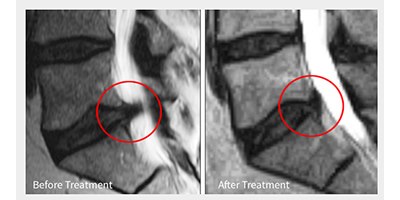

לפני ואחרי טיפול בפריצת דיסק (צילום: ד"ר יואב שטיין)